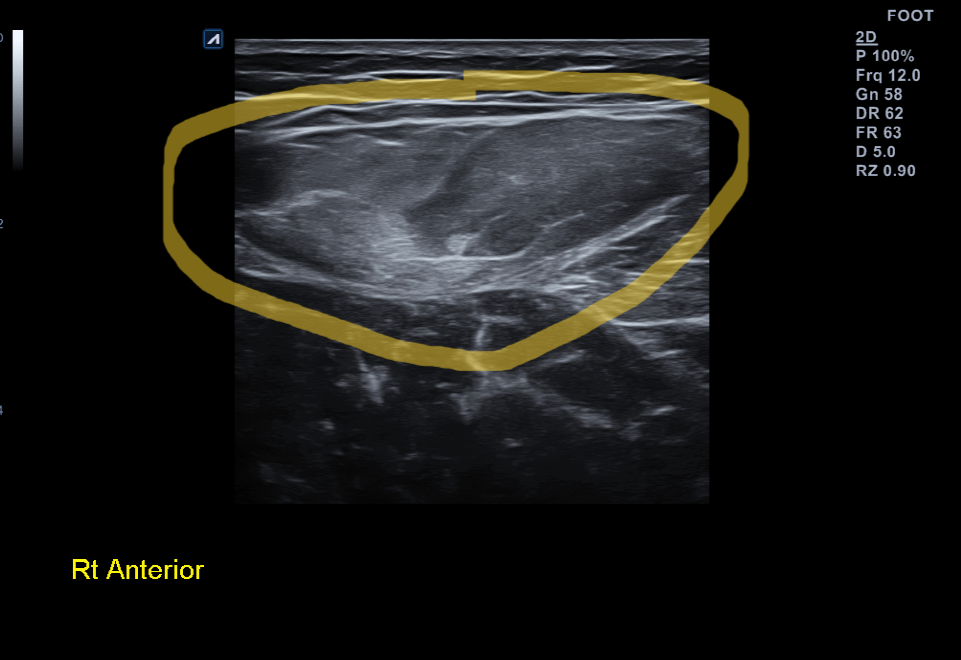

x-ray 검사 상에서는 특별한게 없습니다. 초음파 검사상에서는 근육내 출혈에 의해 양쪽 대퇴직근이 하얗게 (hyperechoic)하게 보이고 있었습니다.

대퇴직근에 출혈이 생겨 초음파 상에서 더 하얗게 보임